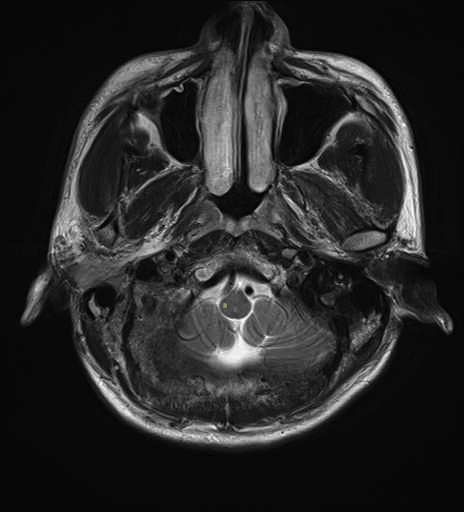

運動系 錐体路系に色を付けました。

■皮質核路:一次運動野から橋及び脊髄神経核まで